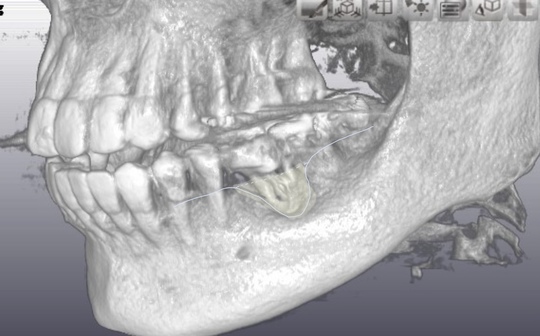

術中

長年の放置で土手の骨が吸収。

自家歯牙移植術

自家歯牙移植(保険治療)、治療回数1回。精密根管治療(自費根管治療)、治療回数2回、治療期間約1週間、治療費(大臼歯初期治療)147,000円+5,000円X1回。ジルコニアクラウン72,000円、治療回数2回。治癒期間含め3ヶ月間。